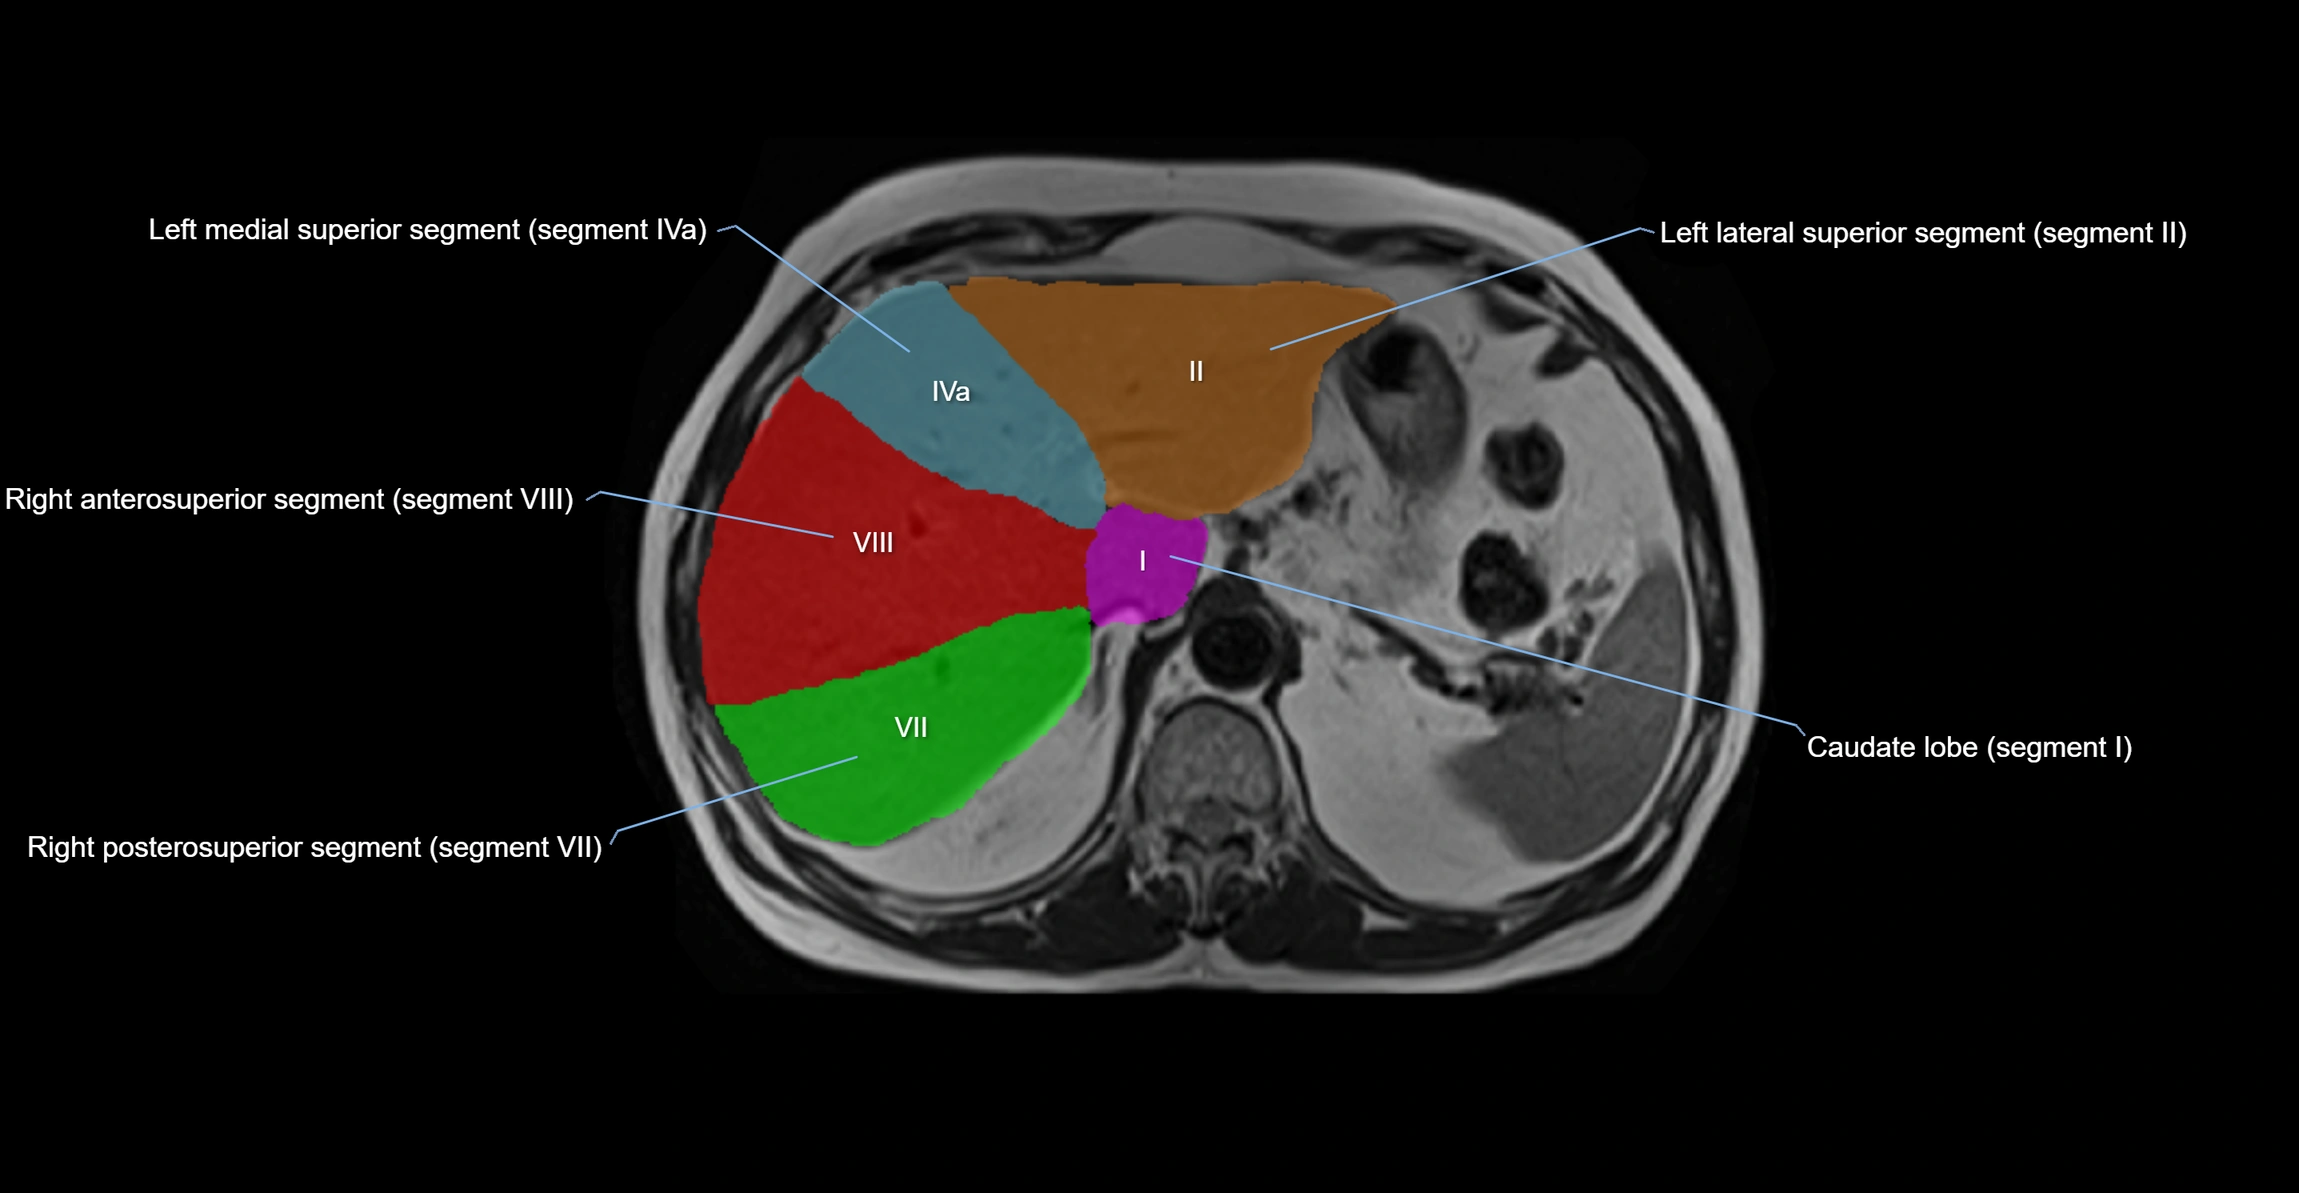

The caudate lobe of the liver is a distinct anatomical subdivision of the liver, designated as segment I in Couinaud’s classification. It lies on the posterior surface of the liver, between the fissure for the ligamentum venosum (left boundary) and the groove for the inferior vena cava (IVC) (right boundary). Superiorly, it is related to the posterior liver surface, and inferiorly it is separated from the left lobe by the porta hepatis.

The caudate lobe is unique because it receives dual portal venous and arterial inflow from both the right and left portal veins and hepatic arteries. It also has independent venous drainage directly into the IVC via multiple small hepatic veins, unlike other lobes that drain through the three main hepatic veins.

This anatomical autonomy makes the caudate lobe especially significant in liver surgery, transplantation, and hepatic venous outflow obstruction syndromes (e.g., Budd–Chiari syndrome). Enlargement of the caudate lobe is a characteristic imaging feature in chronic liver disease and cirrhosis.